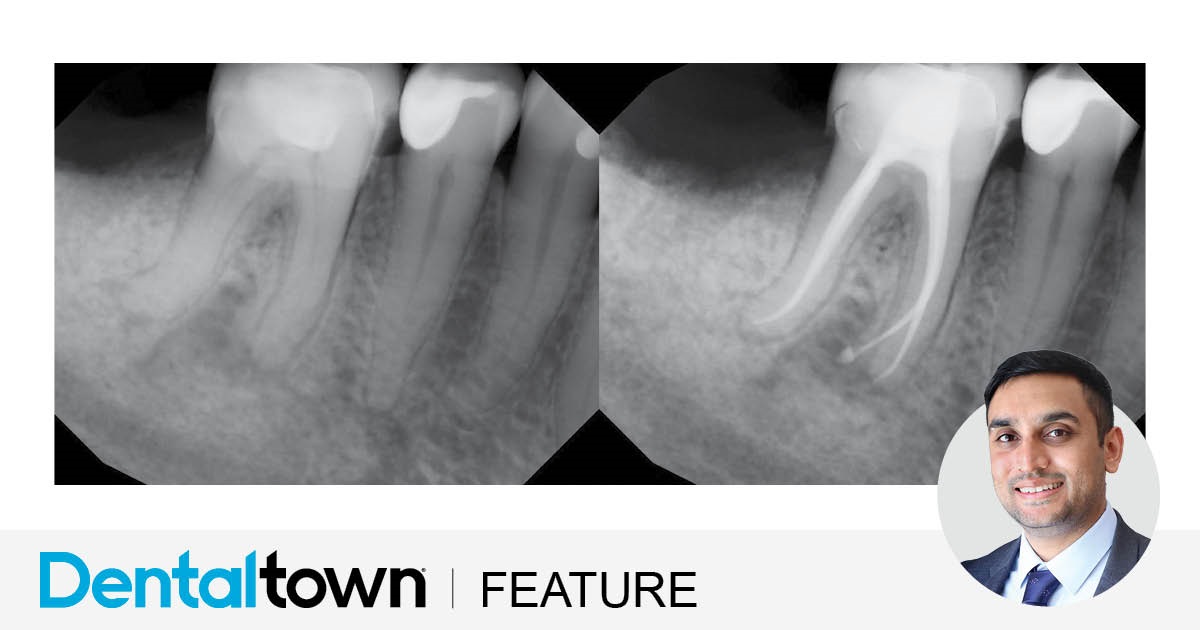

by Dr. Biraj Patel

Dr. Biraj Patel showcases an endodontic case that provided a streamlined, predictable and efficient treatment by utilizing EdgeFile X7 rotary files and EdgeBioCeramic Sealer.